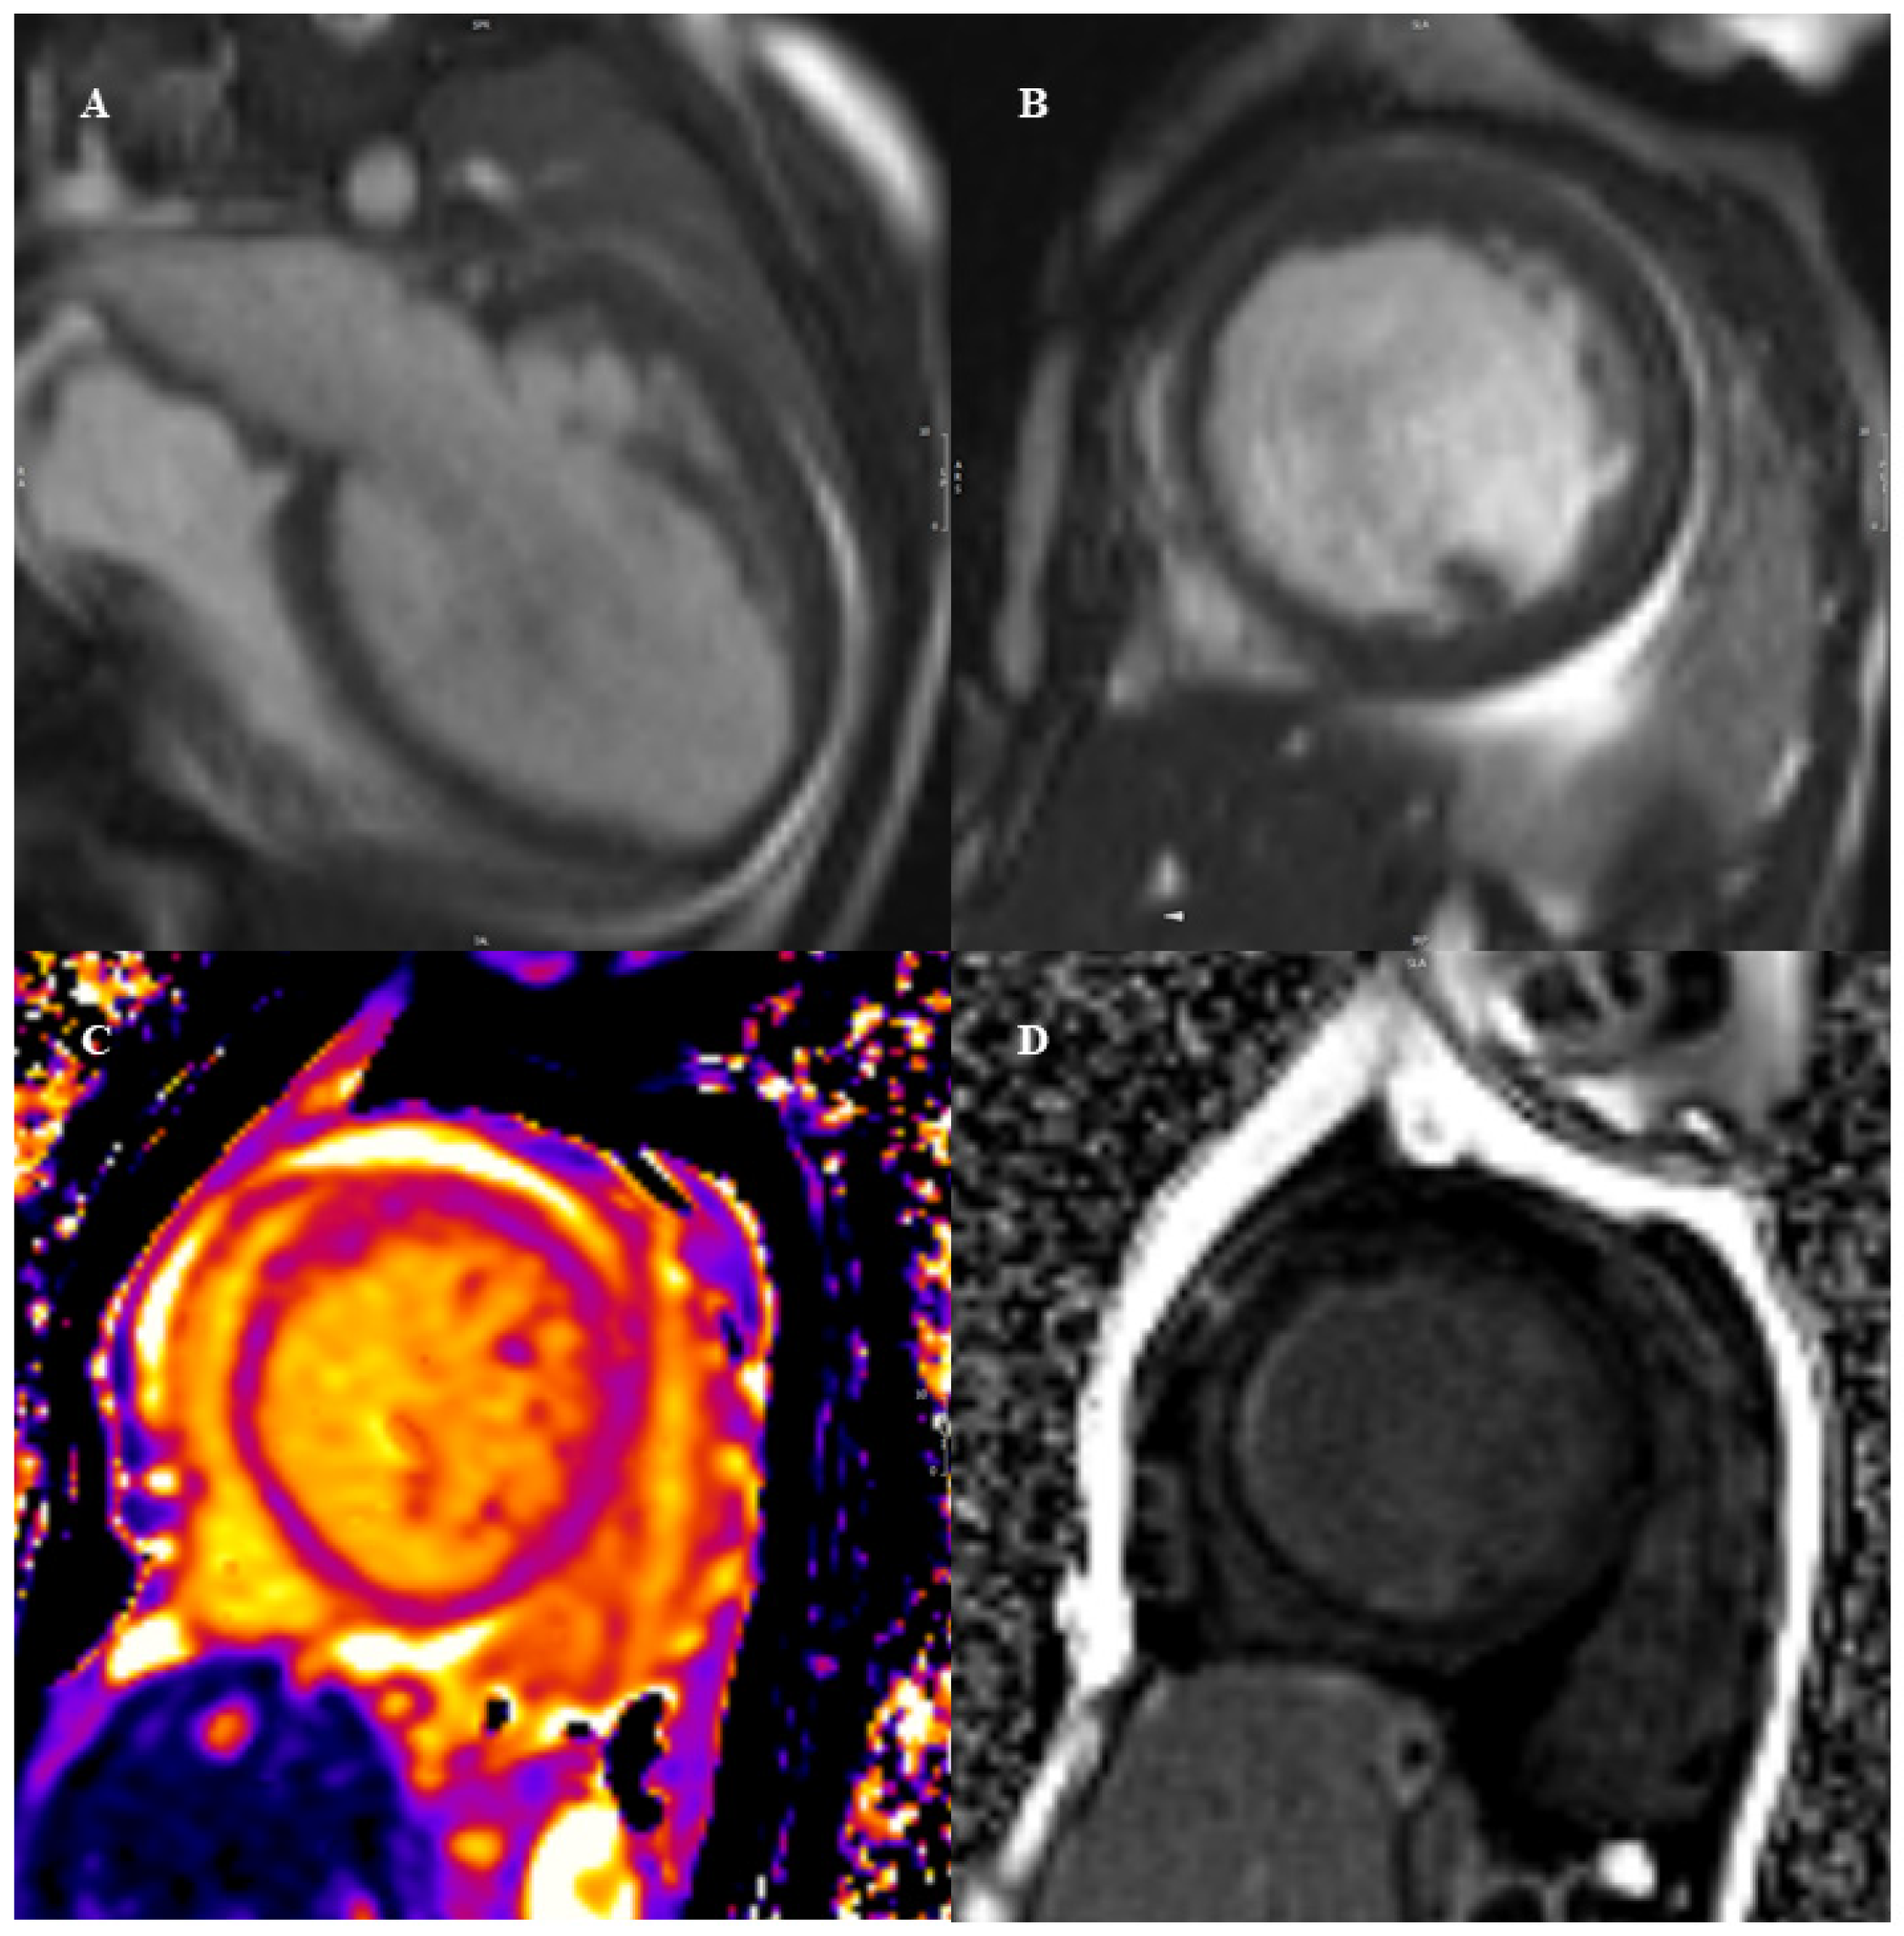

5. Left Ventricular Non-Compaction

CMR Diagnostic and Prognostic Role in Pediatric HCM